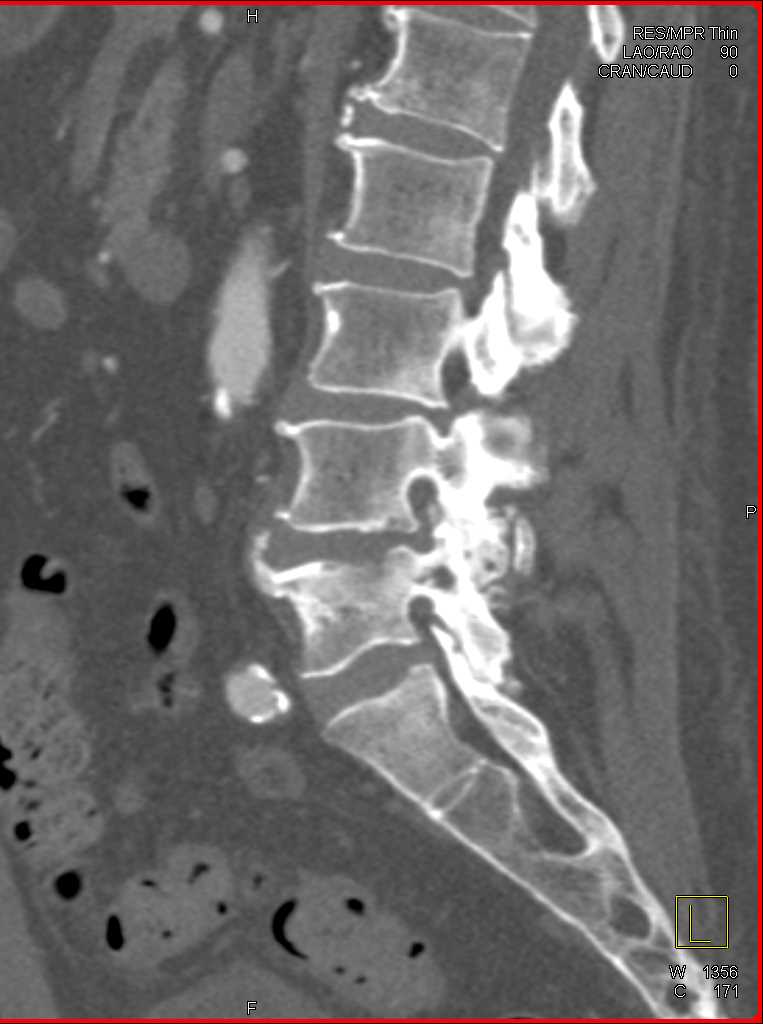

CT appearances and findings are the primary objective for radiologists to determine the accurate diagnosis during reading scans while considering patients' clinical presentation.

This section provides CT appearance for major organ systems and their common malignancies for the radiologists' convenient access that are supplemented with related pearls and lectures from CTisus to enhance radiologists' knowledge for each pathology.

View moreAccess over 322,000 CT Scans and the diagnosis that is identified for each case. The case studies range from CT Scans, MRI, and X-Rays, and are organized by anatomical region: Cardiac, Pancreas, Pediatric, Vascular, Gastrointestinal and more.